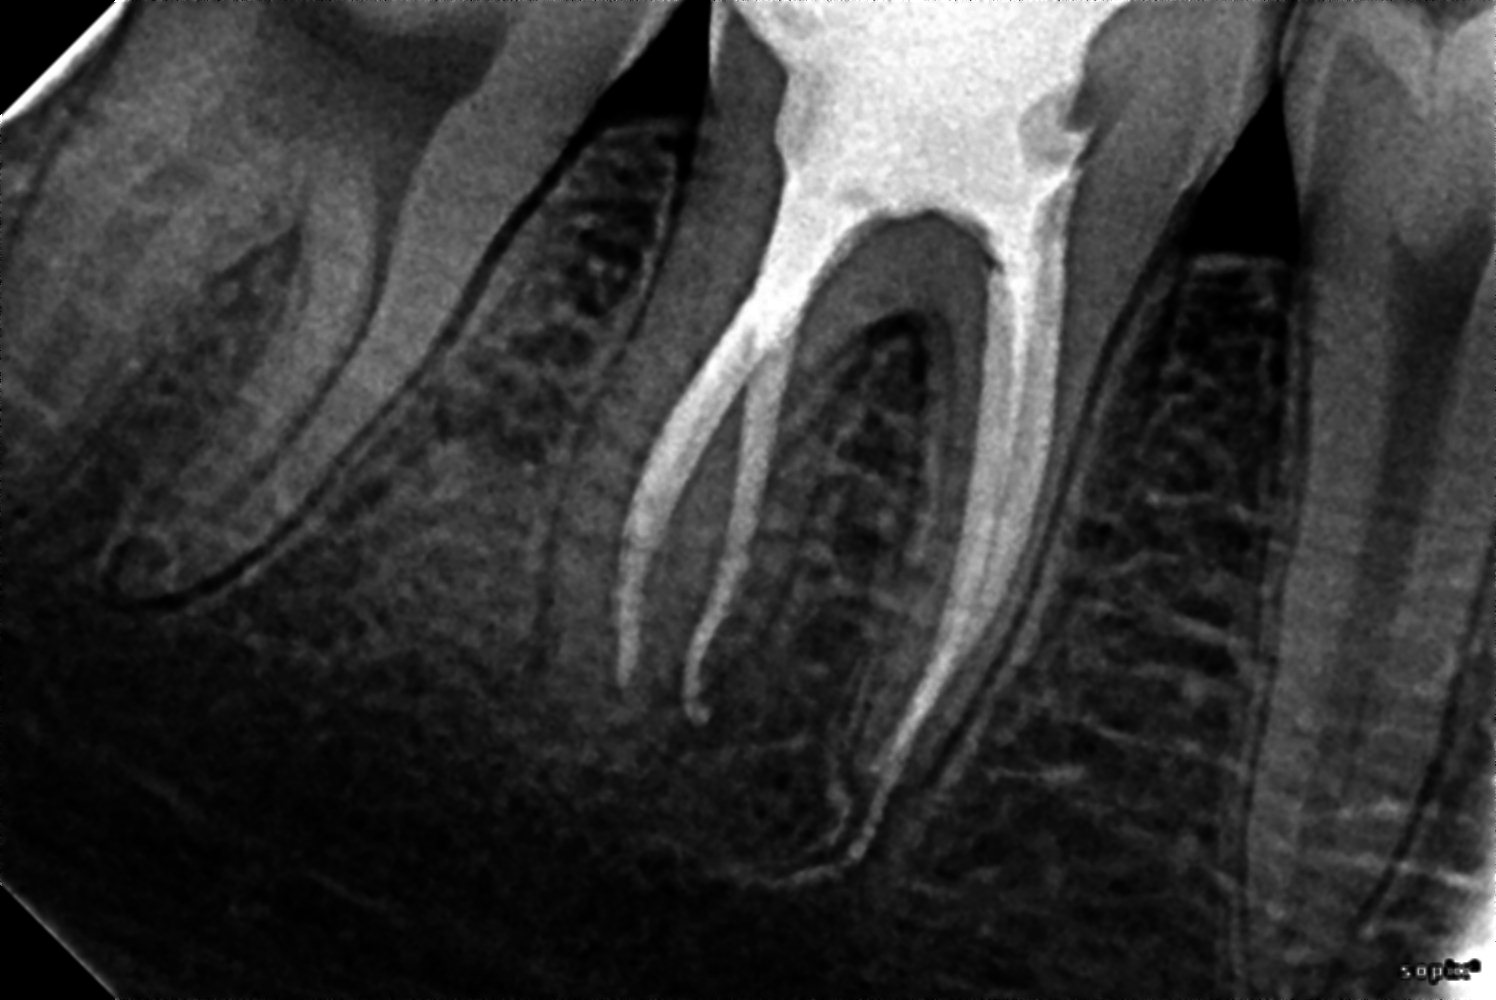

Treatments46 rct done

bioseramic sealer

radix